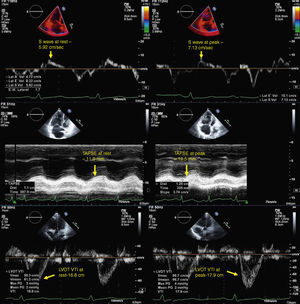

for assessment of RV contractile reserve: in apical 4-chamber view, RV area in diastole (Figure 1) and in systole (to calculate right ventricular fractional area change [RVFAC]), tricuspid annular plane systolic excursion (TAPSE) at the level of the RV free wall, S-wave velocity (with tissue Doppler of the basal segment of the RV free wall), and left ventricular outflow tract (LVOT) velocity-time integral (VTI) (Figure 2). In parasternal long-axis view, LVOT diameter (Figure 1) was assessed only at rest, considering that this dimension does not change with exercise. Stroke volume index (SVI) was calculated on the basis of LVOT diameter, LVOT VTI and BSA.

Figure 2.Echocardiographic parameters of right ventricular contractile reserve in a pulmonary hypertension patient at rest (left) and at peak exercise (right); top – S-wave velocity; middle – TAPSE; bottom – LVOT VTI (used to calculate stroke volume index). LVOT VTI: left ventricular outflow tract velocity-time integral; TAPSE: tricuspid annular plane systolic excursion.